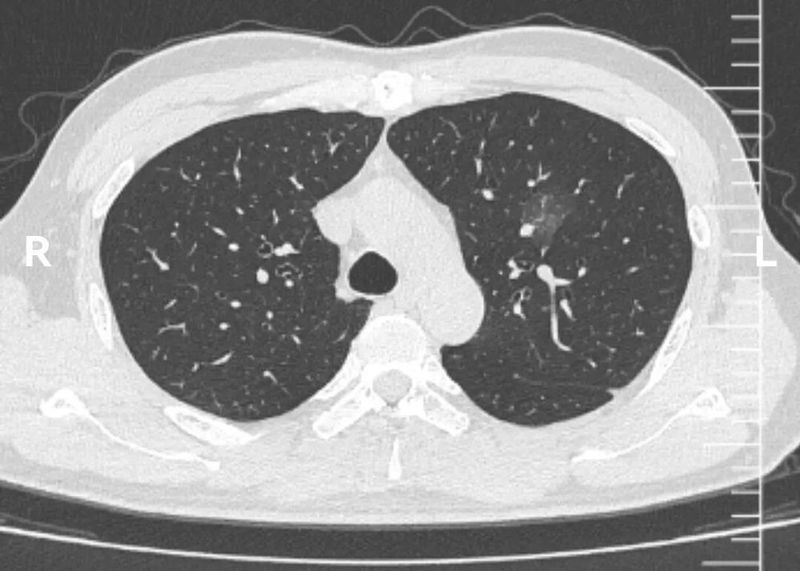

CT图像

这个左上肺混杂磨玻璃结节CT图像非常有特点,首先,磨玻璃成分为主,而且磨玻璃成分边界模糊不清。这本身就是炎症的典型表现。其次,实性成分的形态边界比较清楚,没有分叶、血管异常等形态。

这些CT征象联合一年新出现的病史,已经可以肯定该结节为炎症性,建议患者口服抗生素治疗2周,再一个月复查CT。